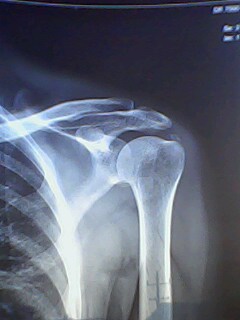

前几天有一个病人因肩痛在别处行针灸治疗,针灸一次后痛点上移至肩关节岗上肌处,并且疼痛加剧彻夜难眠。前天到县医院检查拍了片子,说是肩关节处长骨头需手术治疗。病人不放心今天又到市医院重新检查拍了片子说是岗上肌机化需要封闭治疗。